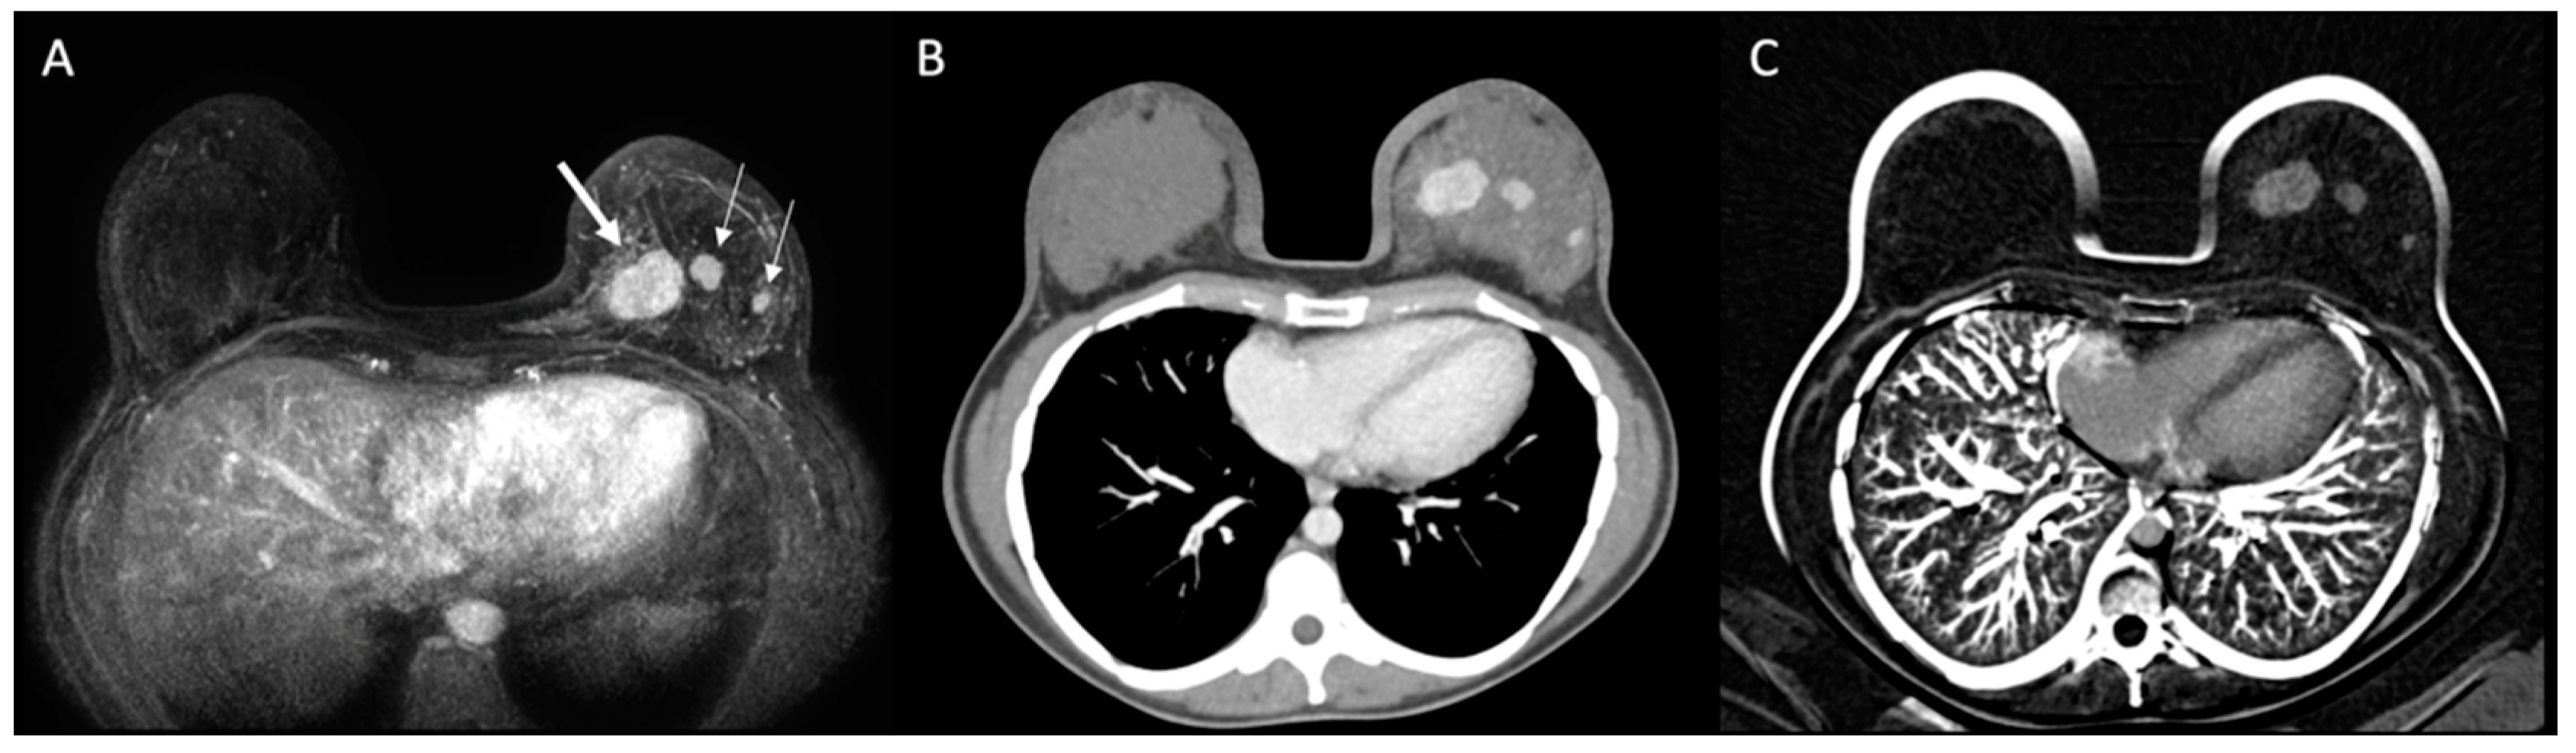

2.3. Imaging Acquisition

MDCT was performed with a specific protocol dedicated to breast evaluation, in prone position, using a specially made device (Figure 1), which reproduces the breast MRI coil. Exams were performed on a 160-slice MDCT scanner (Canon Aquilion Prime 160; Canon Medical Systems, Otawara, Japan), with a 0.5 mm slice thickness, before and after administration of 1–2 mL of the nonionic contrast material ioversol (Optiray 320; Mallinckrodt Medical Inc., St. Louis, MI, USA) per kilogram of body weight intravenously with a semiautomated power injector at a rate of 4 mL/s. The acquisition of chest images was performed 80–90 s after the contrast administration, which was previously reported as the optimal delay time to depict breast cancer [21]. Pre-contrast images were digitally subtracted from post-contrast images using a motion correction software (Sure Subtraction; Canon Medical Systems, Otawara, Japan) to improve the evaluation of enhancing lesions in the breast parenchyma and color-coded iodine maps were performed (Figure 2).

Figure 1. Example of chest multidetector computed tomography (MDCT) with dedicated breast protocol. (A) Device used to perform chest MDCT on prone position. (B) Axial image of conventional chest MDCT in supine position. (C) Axial image of the breast in the same patient using dedicated MDCT protocol in prone position.